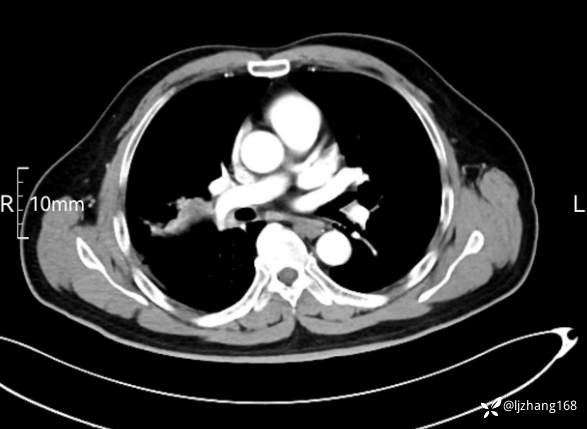

中年男患,右肺团片影,炎症0R肿瘤?

辅助检查:糖化血红蛋白12.3%。肺炎支原体IgG、IgM、呼吸道合胞病毒均未见明显异常。胸部CT:右肺上叶阻塞性肺炎。